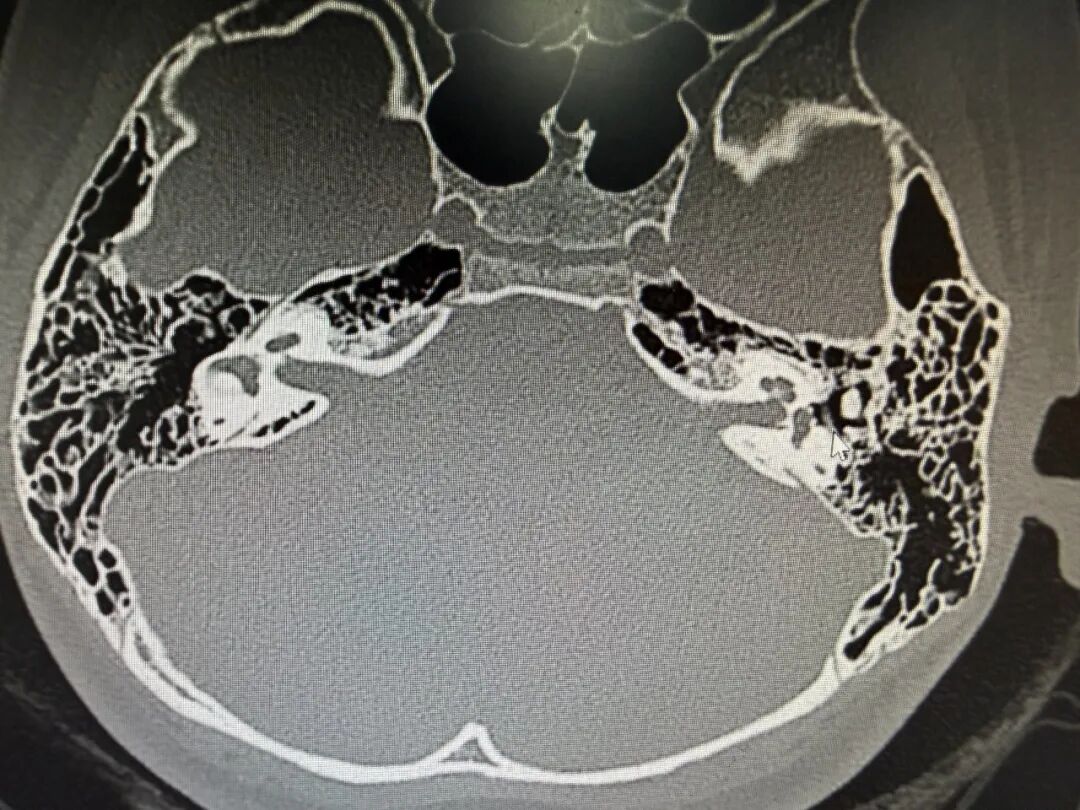

显微镜下,丁医生仔细磨除外耳道闭锁区域的骨质,一点一点开辟出新的外耳道。通道打通后,手术团队精准植入了一块全钛人工听骨,重新构建起声音传导的“桥梁”。

术后检查显示,女孩的听力得到了大幅改善,更重要的是,面神经功能完好无损,没有出现任何并发症。